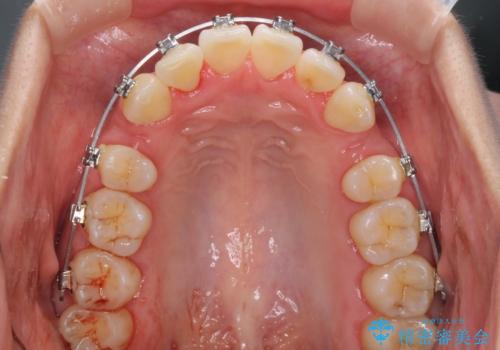

前歯のデコボコを治したい 費用を抑えた抜歯矯正

- メタルブラケット

- 2年8ヶ月

- 上下前歯のでこぼこを気にされ、矯正治療を希望された患者様です。

費用を抑えるため、メタルブラケットを採用し、抜歯矯正を行うこととしました。

通常であれば、上下顎左右小臼歯各1歯の合計4本を抜歯しますが、歯肉退縮の著しい下顎前歯を抜歯して欲しいという患者様の強い希望により、上顎のみ左右小臼歯2歯を、下顎は前歯を1歯を抜歯することとしました。

抜歯する歯を変更したため奥歯の咬合はアンバランスとなりましたが、前歯は綺麗に整い、歯肉退縮も回避できました。